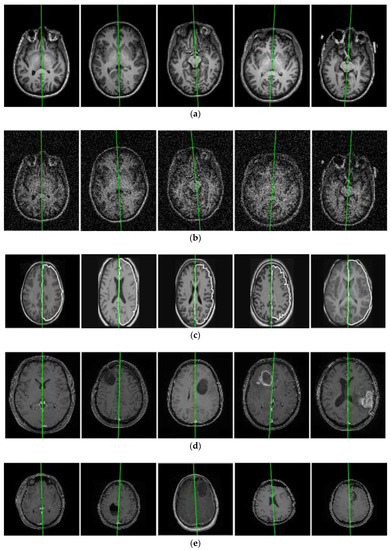

3.1. Evaluation on Real Datasets

The MSP is extracted from each dataset using the proposed algorithm and some slices perpendicular to the estimated MSP are snipped and displayed in Figure 9. The green line in each image is the intersecting line between the estimated MSP and the corresponding orthogonal slice. The first row (Figure 9a) represents the images from the NFBS database with extracted MSP by the proposed algorithm. The images of the same dataset (NFBS) are synthetically degraded by adding zero-mean Gaussian noise of several levels. Proposed algorithm breaking points can be found by incrementally adding the noise until the algorithm fails to detect the accurate MSP plane. The proposed algorithm successfully estimated the MSP at levels of noise up to SNR = −10.09 decibel (dB). The second row (Figure 9b) indicates representative resulting slices and the estimated MSP from noisy images. Images from the IBSR database are portrayed in Figure 9c. Manual delineation (GT) of brain hemispheres is available only for the IBSR database. The manual delineation boundary is superimposed on the input image with the white pixels by using a morphological gradient and binary skeletonization [51], as shown in Figure 9c. The proposed algorithm successfully extracts the MSP in all the volumes of the IBSR database and no obvious error is detected. The last two rows in Figure 9 contain the MSP-extracted results from the MNI BITE database. Group 2 (Figure 9d) comprises pre-operative MRIs and Group 3 (Figure 9e) includes MRIs acquired at different intervals of time, i.e., before and after surgery. Obvious asymmetries can be seen in the two groups of brain MRIs. The proposed algorithm extracted the symmetry axes from these volumes robustly and accurately.

Figure 9.

Visual comparison of the proposed algorithm in extracting the symmetric axis (MSP) from real brain MRIs, (a) the NFBS database [38], (b) images of the same subjects with Gaussian noise, (c) the IBSR database [39], (d) the MNI BITE database Group 2, and (e) the MNI BITE database Group 3 [40].